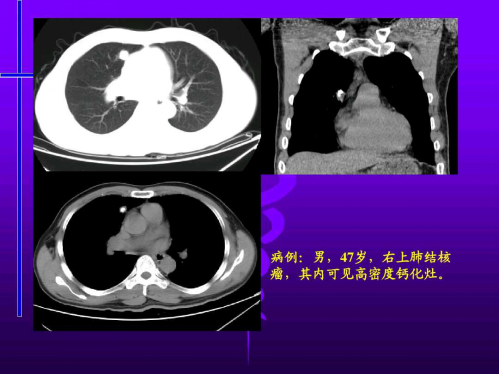

恶性疾病主要包括肺腺癌、细支气管肺泡癌和肺鳞状细胞癌。主要良性疾病包括:肺错构瘤、肺硬化性血管瘤、炎性假瘤、肺结核瘤、肺曲霉菌病、血管滤泡淋巴结增生。